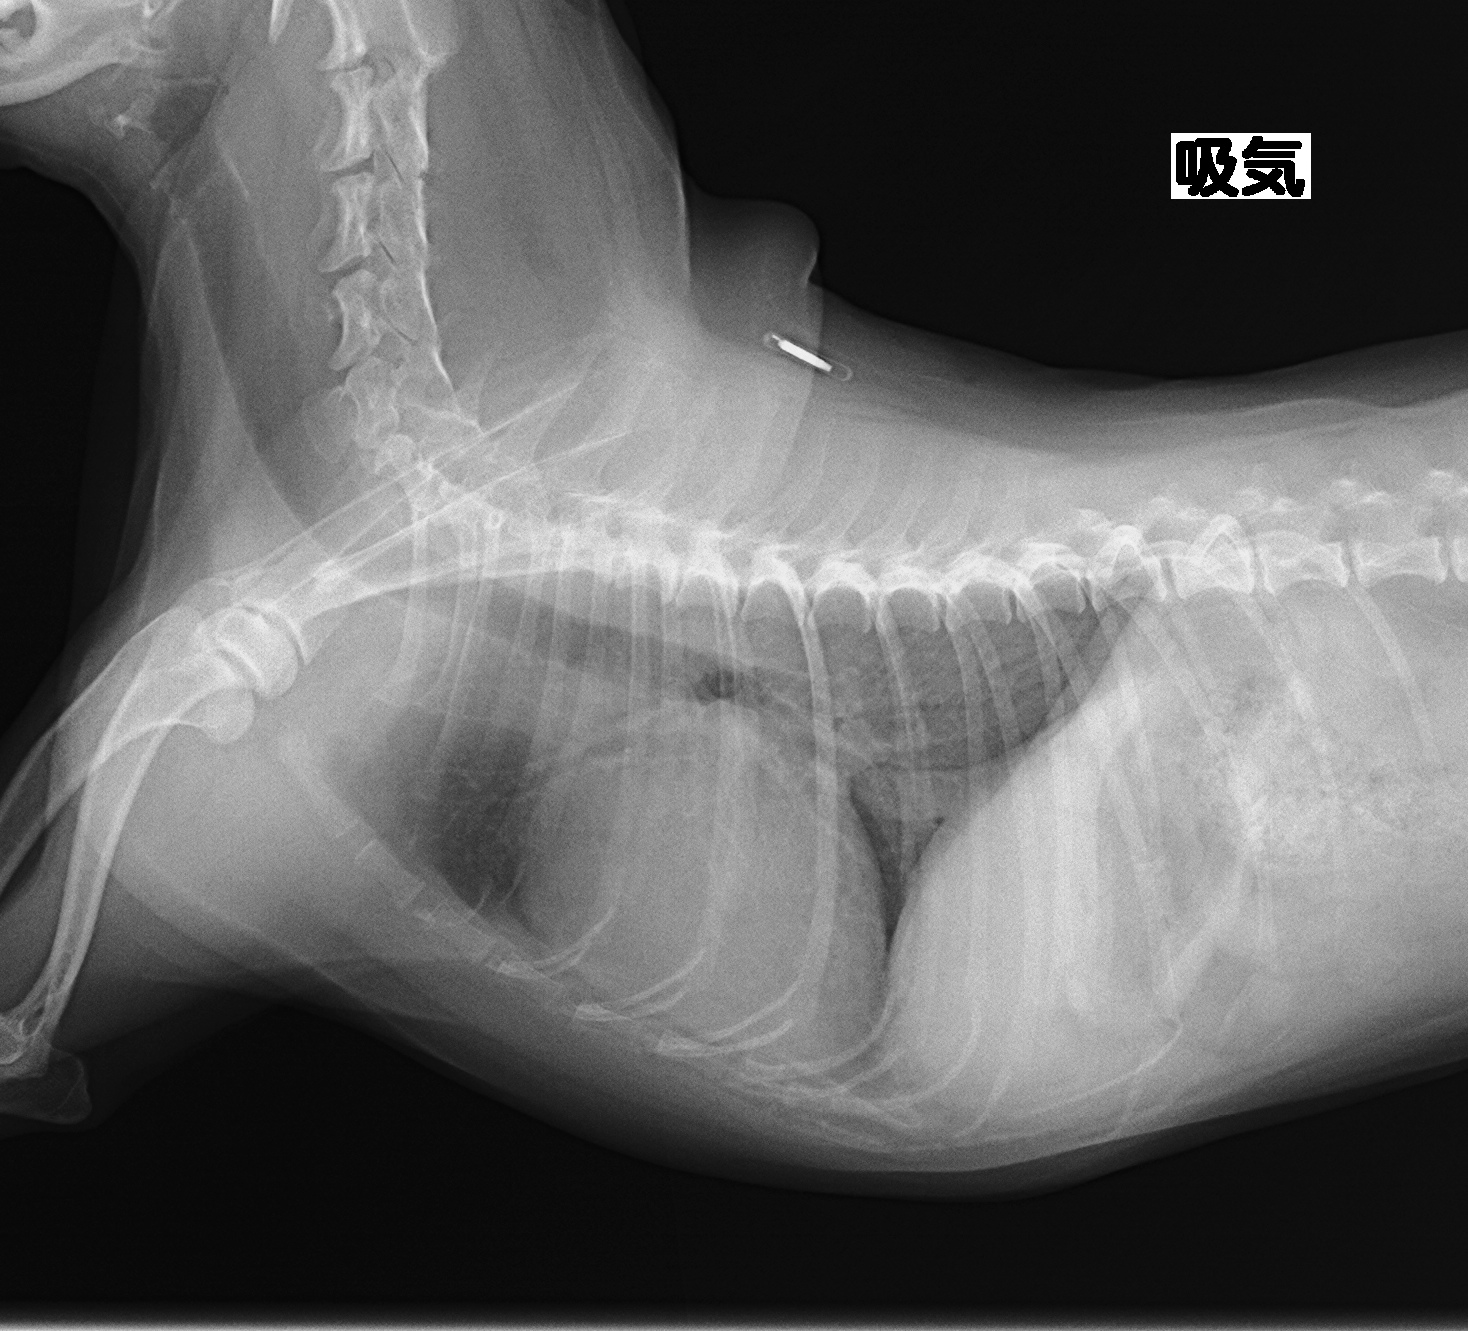

→さらに進行し心不全の症状として肺水腫を発症した段階です。心不全(肺のうっ血)により肺に水が溜まり呼吸困難を呈した状態となっていて、ステージB2よりさらに複数の薬剤での治療が必要不可欠となります。

画像は前述の写真と同じ子の別時期のものです。肺に水がたまり(肺水腫)肺が白く写っています。息苦しさに気づき来院されました。